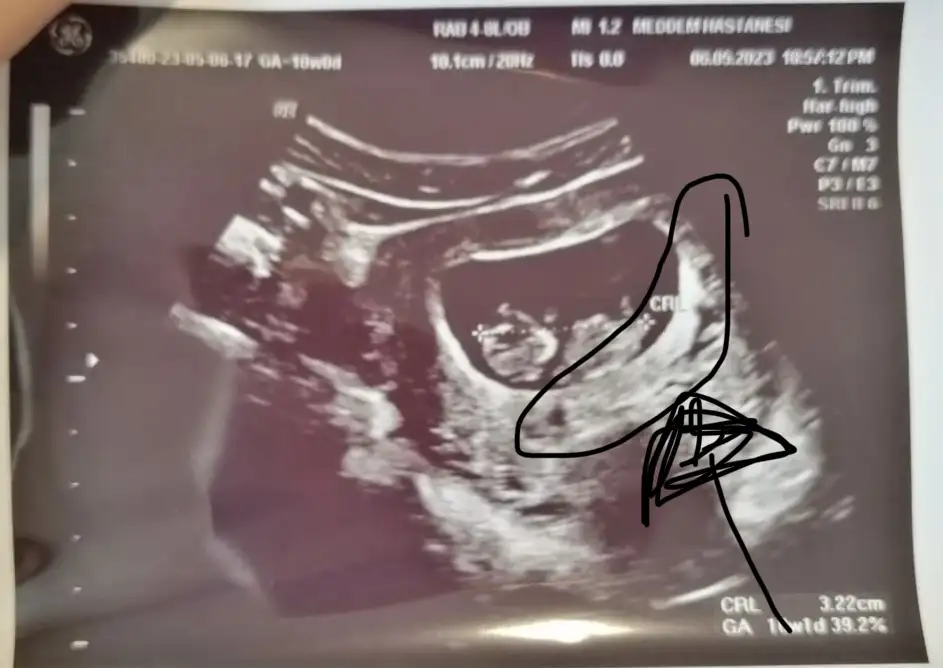

Evet kadın doğum doktoru baktı canım , damar genişlemesi olabilir. Belki bir yara vardı o kanama yapmış olabilir , Corasprin kaynaklı olabilir , üstüne görme olabilir dedi, ama alanda hiç bir kanama görmedi hatta bebişin gelişimi de 3gün ilerde imiş .